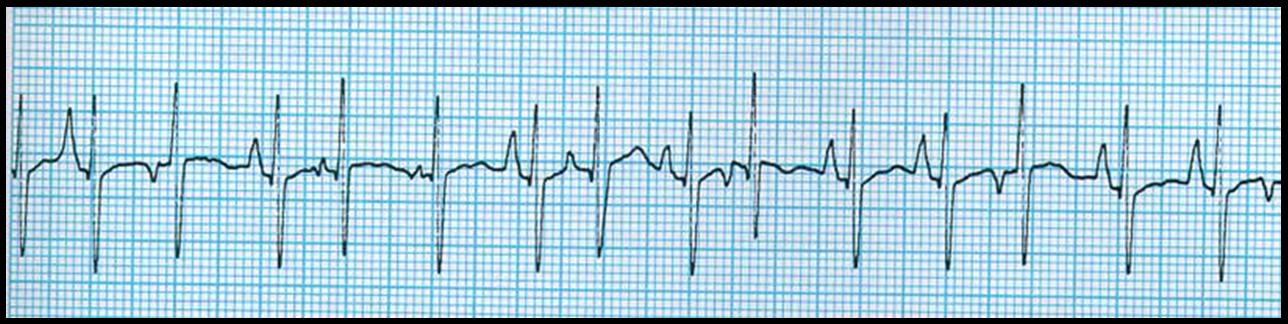

Atrial Fibrillation Atrial fibrillation, often called AFib or AF, is the most common type of heart arrhythmia. An arrhythmia is when . the heart beats too slowly, too fast, or in an irregular way. ... View Document

WHAT IS ATRIAL FIBRILLATION? In atrial fibrillation, the heartbeat is irregular and rapid, sometimes beating as often as 300 times a minute in the upper chambers (atria) and 100-150 times a minute ... Document Retrieval

Fibrillation is the rapid, irregular, and unsynchronized contraction of muscle fibers. An important occurrence is with regard to the heart. Cardiology. There are two major classes of cardiac fibrillation: atrial fibrillation and ventricular fibrillation. ... Read Article